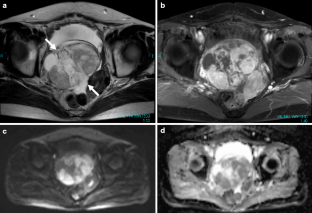

Fig. 4a–d